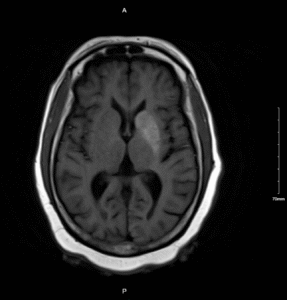

Nonketotic Hyperglycemia Hemichorea. MRI Unnnotated. JETem 2025